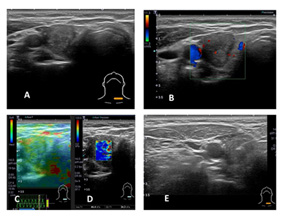

頸部超音波為首選檢查,可評估結構、血流及腫瘤特徵;若懷疑惡性,則需進行超音波導引細針穿刺(FNA),並依照 Bethesda 細胞分類系統判讀結果,以決定後續追蹤或手術治療。若確診為甲狀腺癌,術前也需完整評估頸部淋巴結,以規劃手術範圍。

圖一、典型的甲狀腺癌超音波表現;A.氣管左側甲狀腺結節出現微鈣化及垂直於皮膚的形狀。B.血流豐富、呈現不規則形狀。C&D.彈性超音波呈現較硬的結節。E.即時超音波導引下,目視針尖進入甲狀腺結節進行細針穿刺細胞學檢查。